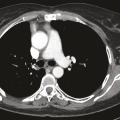

Une imagerie par résonance magnétique (IRM) du crâne réalisée 15 jours après le début des symptômes n’a pas montré d’anomalie. Toutefois, leur persistance et leur aggravation ont fait demander à son médecin traitant un dosage des anticorps antirécepteurs à l’acétylcholine, qui s’est révélé positif, conduisant au diagnostic de myasthénie. Des anticholinestérasiques ont alors été prescrits en première intention, permettant d’améliorer transitoirement les symptômes musculaires. Leur effet est de prolonger l’action de l’acétylcholine au niveau de la membrane post-synaptique par blocage réversible de l’acétylcholinestérase (deux médicaments sont disponibles : la pyridostigmine et l’ambénomium). Dans le cadre du bilan de cette myasthénie, une tomodensitométrie thoracique est pratiquée, qui met en évidence une masse médiastinale antérieure, volumineuse et polylobée évoquant une tumeur thymique (fig. 1).1